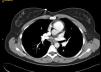

Al igual que la paciente anterior, ante la sospecha de TEP, se deriva a urgencias del hospital de referencia donde se realizan las siguientes pruebas:

Hemograma, bioquímica y gasometría arterial con valores dentro de la normalidad; coagulación: normal salvo un dímero de 421; radiografía de tórax: silueta cardíaca izquierda ligeramente rectificada con derrame pleural izquierdo. TC torácica (fig. 2): TEP bilateral con posible infarto periférico en língula y pequeño derrame pleural izquierdo.